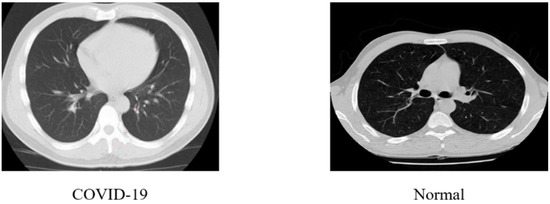

3.1. Dataset Description